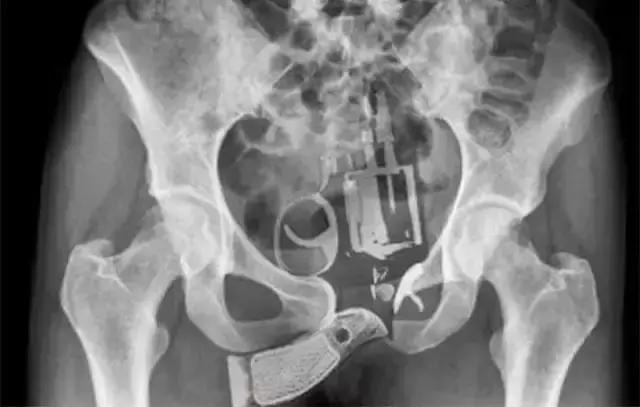

7、不法分子真是能铤而走险,连枪都敢往里面塞!